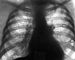

На рентгенограммах при выраженном воспалительном процессе во внутригрудных лимфатических узлах тень корня легкого уплотнена, расширена. деформирована и дислоцирована, контуры ее нечеткие, полицикличные, главный и долевые бронхи четко не выявляются (рис. 3, а, б), в лимфатических узлах иногда видны точечные обызвествления. Особенно отчетливо эти симптомы определяются на томограммах, выполненных в плоскости расположения главных бронхов (рис. 3, в). При туберкулезе околотрахеальных и трахеобронхиальных лимфатических узлов тень средостения обычно расширена, контуры ее зависят от выраженности патологических изменений. Рентгенологическими признаками малых форм туберкулеза внутригрудных лимфатических узлов являются видоизменение легочного рисунка, его спутанность, деформация корня легкого. Неактивный туберкулезный бронхаденит рентгенологически характеризуется наличием во внутригрудных лимфатических узлах мелких кальцинатов, деформацией и фибротизацией корня легкого.